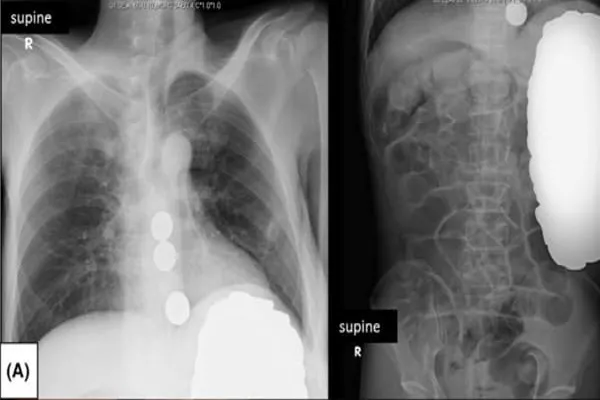

L’uomo giapponese si è presentato al centro medico di Tokyo, presentava fatica cronica e aveva l’addome teso e dolorante. I medici lo hanno sottoposto ad una radiografia che ha rilevato la presenza di corpi estranei. Immediatamente è stato trasferito in un centro chirurgico dove i chirurghi hanno trovato un piccolo buco di circa 5 mm di diametro, dal quale sono riusciti ad asportare circa 2mila monetine.

Il quantitativo di monete estratte era enorme e per fortuna l’uomo non è stato intossicato dalla presenza degli oggetti di metallo. Dopo l’operazione, il paziente è stato trasferito presso un centro psichiatrico. Secondo quanto riferito dai media locali in passato ha sofferto di depressione ed è affetto da schizofrenia. Sono stati registrati almeno 6 casi di sindrome di Pica, ma questa è la prima volta in assoluto che viene accertata la perforazione gastrica. In passato un paziente indiano aveva ingerito 7 kg di metallo, un americano 600 monete, quello del 51enne giapponese è un vero e proprio record.